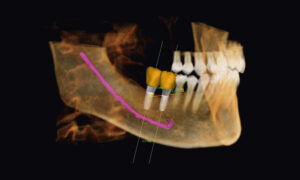

This technology provides highly accurate 3D radiographic images for the diagnosis, planning and treatment of dental implantology, TMJ analysis, airway assessment, oral and orthognathic surgery and other dental procedures.

Three-dimensional images enable a level of anatomical accuracy and patient care not possible with 2-D technologies. With the addition of cone-beam CT technology in our office, our practice is committed to providing innovative, high-quality, patient care.